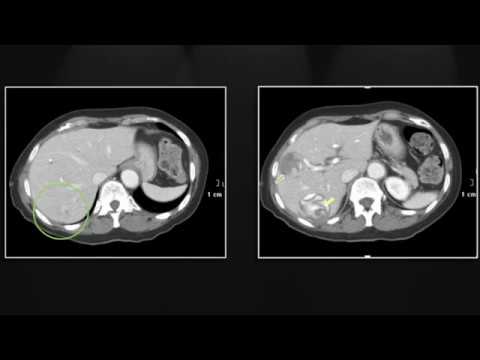

HỘI CHỨNG FITZ-HUGH-CURTIS. Thread starter BOT2; Start date Nov 26, 2016; B. BOT2 Administrator. Staff member. Nov 26, 2016 #1 Nữ 36 tuổi. Đau toàn bụng ngày thứ nhất, không phản ứng thành bụng. Đi cầ

Hội chứng Fitz-Hugh-Curtis là viêm phúc mạc khu trú chủ yếu ở bao gan có liên quan đến bệnh lý viêm nhiễm vùng tiểu khung ở phụ nữ. Chẩn đoán gặp khó khăn vì dễ nhầm với các bệnh lý bụng cấp tính khác

Hội chứng Fitz-Hugh-Curtis (FHC) là biến chứng hiếm của viêm nhiễm vùng tiểu khung biểu hiện bằng đau hạ sườn phải do viêm quanh gan [2], [3]. Về lâm sàng, biểu hiện đau bụng hạ sườn phải do viêm...

May 23, 2022Hội chứng Fitz-Hugh-Curtis (FHC) là biến chứng hiếm của viêm nhiễm vùng tiểu khung của nữ giới biểu hiện bằng đau hạ sườn phải do viêm quanh gan [2], [3]. Về lâm sàng, biểu hiện đau bụng h